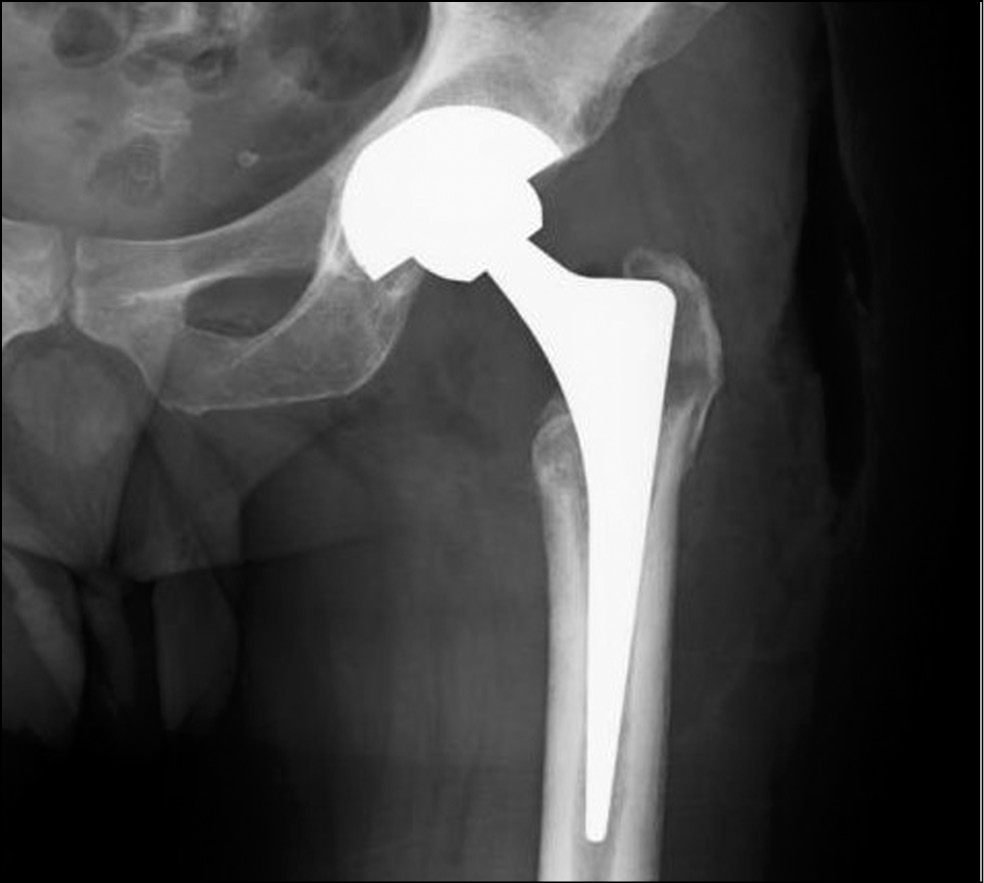

Головка и шейка бедра вывихнуты в операционную рану. Суставной хрящ головки бедренной кости практически отсутствует, качество костной ткани головки, шейки и проксимального метаэпифиза бедренной кости резко снижено. При осуществлении вывиха произошёл патологический перелом (продольный раскол) в области шейки бедренной кости. Был произведён остеосинтез металлофиксатором (винтом). Выполнена шаблонная резекция шейки бедра, головка удалена. Произведено освобождение вертлужной впадины от фиброзно изменённых мягких тканей, с помощью риммеров осуществлено удаление патологически изменённого суставного хряща и субхондральной костной ткани вертлужной впадины. Перед установкой спейсера выполнены санация, ультразвуковая кавитация вертлужной впадины, параартикулярных тканей с раствором бетадина (в концентрации 1,3 г/л). К костному цементу Surgical Simplex P (40 г) добавлено 2 г порошка ванкомицина и 2 г порошка цефтриаксона, и смоделирован шаровидный спейсер. В качестве ориентира для формирования спейсера необходимого диаметра мы использовали риммер, которым предварительно определили диаметр вертлужной впадины (в нашем случае диаметр составлял 47 мм). Сформированный спейсер помещён в вертлужную впадину. После вправления проведена ревизия: объём пассивных движений в пределах физиологической нормы, тенденции к миграции спейсера нет. Операция завершена послойным ушиванием раны без оставления дренажей. На контрольной рентгенограмме определяется цементный шаровидный спейсер в вертлужной впадине (рис. 3).

Рис. 3. Послеоперационная контрольная рентгенограмма пациента С., 38 лет, на 5-е сутки после операции.